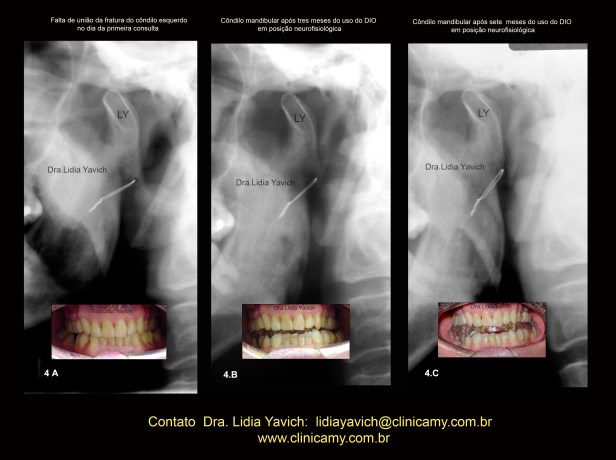

Uma segunda radiografia panorâmica foi solicitada três meses após o inicio do tratamento.

A nova radiografia panorâmica mostrou a melhora da posição do côndilo mandibular e finalmente quatro meses após este ultimo controle uma terceira radiografia panorâmica foi solicitada onde pode se observar a união da fratura.

Imagem comparativa do côndilo mandibular esquerdo na primeira radiografia panorâmica do paciente no dia da consulta (4A).

Segunda radiografia panorâmica três meses após (4B)

Terceira radiografia panorâmica (4C) quatro meses após o segundo controle mostrando a melhora da posição do côndilo mandibular e a união do osso.

OBSERVAR A VERTICALIZAÇÃO DO FIO METÁLICO DA CIRURGIA

INVERSÃO DA COR da imagem comparativa do côndilo mandibular esquerdo na primeira radiografia panorâmica do paciente no dia da consulta (4A), segunda radiografia panorâmica três meses após (4B) e terceira radiografia panorâmica (4C) quatro meses após o segundo controle mostrando a melhora da posição do côndilo mandibular e a união do osso.

OBSERVAR A VERTICALIZAÇÃO DO FIO METÁLICO DA CIRURGIA.

Imagem comparativa do côndilo mandibular esquerdo na primeira radiografia panorâmica do paciente no dia da consulta (4A), segunda radiografia panorâmica três meses após (4B) e terceira radiografia panorâmica (4C) quatro meses após o segundo controle mostrando a melhora da posição do côndilo mandibular e a união do osso.

As imagens frontais da oclusão habitual no dia da consulta, quatro e sete meses após iniciado o tratamento estão também inseridas nesta imagem.